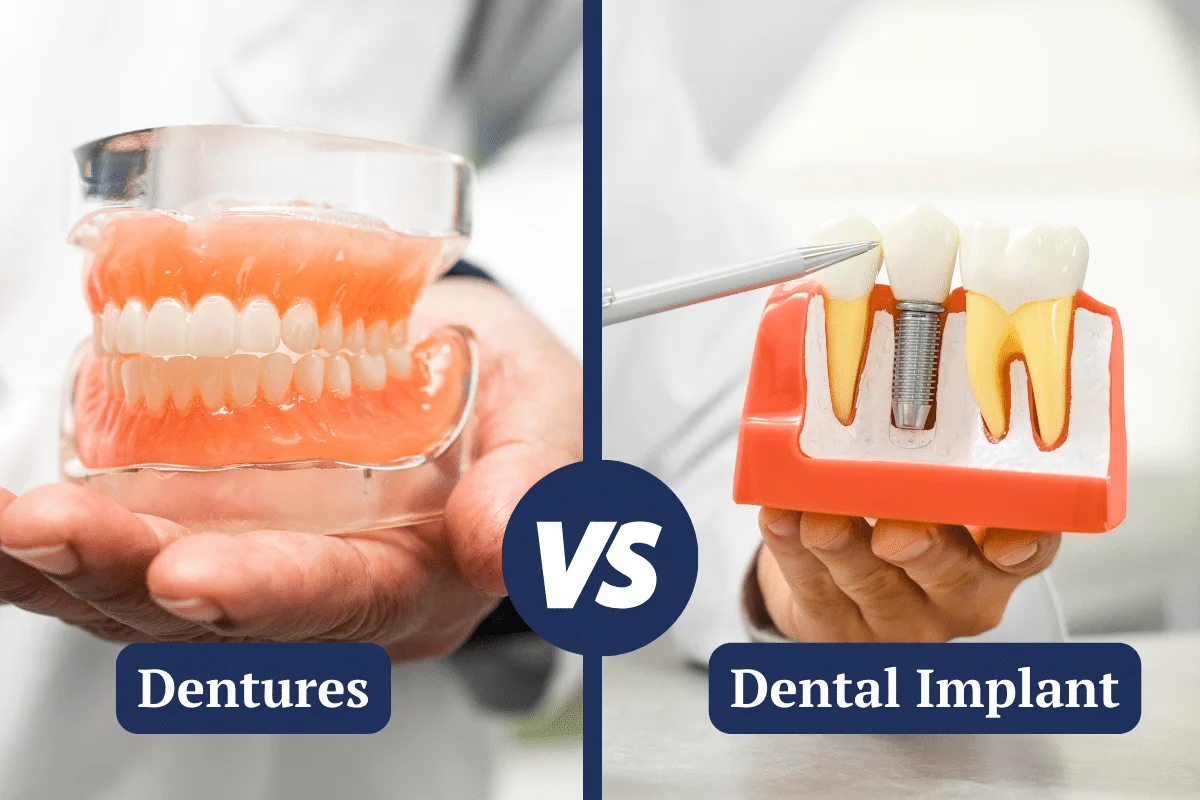

مهارتهای عملی، مکمل دانش تئوری هستند. بهترین متخصص باید تجربه زیادی در انجام جراحیهایی مانند جراحی فلپ، پیوند لثه، افزایش طول تاج دندان، درمان لبخند لثهای و کاشت ایمپلنت داشته باشد.

6. کاشت ایمپلنت دندانی با تکنیکهای پیشرفته